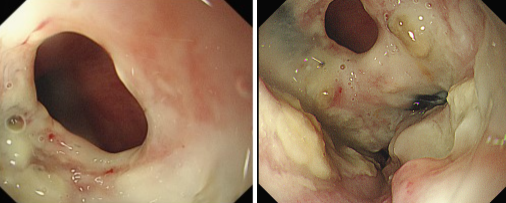

品質(zhì)國(guó)文 | 重獲進(jìn)食希望——內(nèi)鏡下食管覆膜支架植入手術(shù)

張大爺近期突然遭遇進(jìn)食困難,還頻繁出現(xiàn)進(jìn)食嗆咳的狀況。緊急檢查后,確診為食管惡性腫瘤,同時(shí)并發(fā)食管氣管瘺,而且因食物誤吸引發(fā)了肺部感染。由于瘺口的存在,食物不斷進(jìn)入氣道,致使嗆咳加劇、感染惡化,這不僅嚴(yán)重降低了張大爺?shù)纳钯|(zhì)量,更對(duì)其生命構(gòu)成了極大威脅。 閱讀量:1216